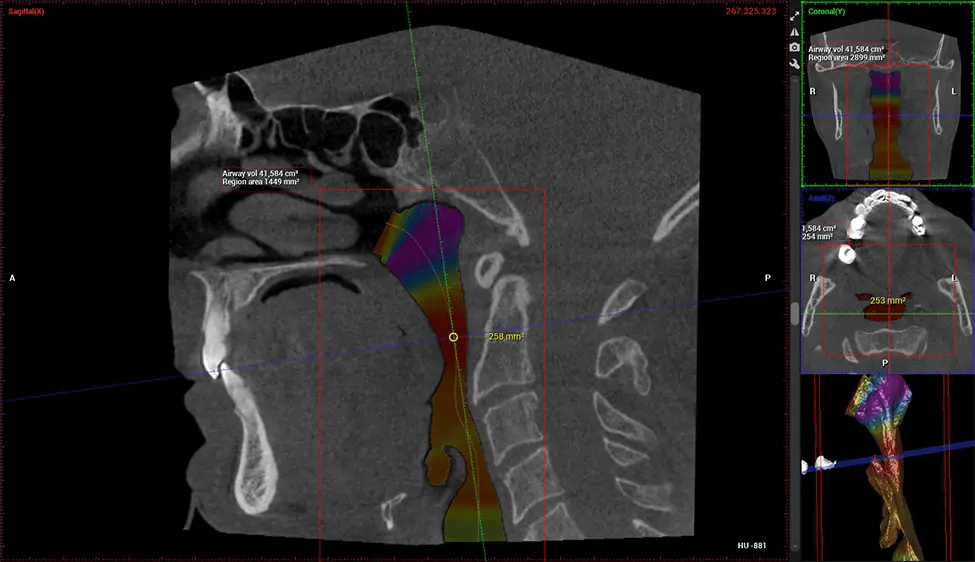

After the scanning process, the captured X-ray images are processed by the CBCT software, which applies algorithms to reconstruct a detailed 3D image of the scanned area. The software compiles these individual X-ray images and creates a digital 3D representation of the patient’s anatomy. The reconstructed 3D CBCT image can be viewed and analyzed by the dentist or radiologist. This image can be manipulated, rotated, and zoomed in or out to examine specific structures and evaluate the patient’s condition.

Planmeca Viso G7 CBCT ( Cone Beam CT Scan ) is designed to surpass the demands of industry leaders, specialists, and large institutions. It’s has a large ø25×30 cm sensor with four built-in cameras. It can capture unlimited volume sizes from a ø3×3 cm to a ø30x30cm volume capturing the skullcap through C7 on the cervical spine. The Planmeca Viso G7 offers the industry’s largest single volume scan of ø30×19 cm. It’s poised to handle advanced imaging modalities such as Planmeca ProFace® and Planmeca 4D™ Jaw Motion technology. The occipital head support allows an unimpeded view of facial tissue.